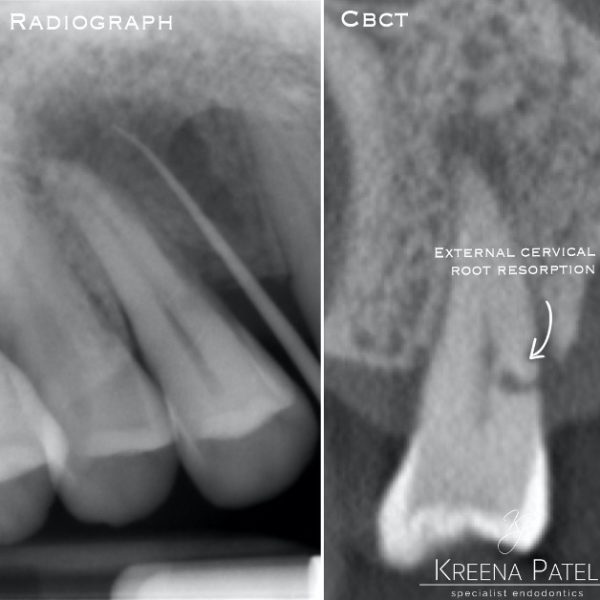

The root of the problem external cervical resorption Dentistry Online What Causes External Resorption In Teeth Empirically, ecr is the form of resorption most often seen in clinical dental practice. There are several factors that may lead to resorption of teeth. External resorption starts at the border of the tooth’s root structure on the outside of the tooth and works its way in. This may include a night guard. External resorption is a condition that leads. What Causes External Resorption In Teeth.

From www.kpteeth.co.uk